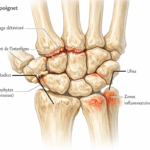

Arthrose du poignet

L’arthrose résulte de l’usure du cartilage. Elle est souvent secondaire à un traumatisme ancien ou à une maladie inflammatoire. Elle provoque :

- douleur mécanique,

- raideur articulaire,

- craquements.

Radiographie, échographie, IRM

Selon les cas, le spécialiste peut prescrire :

- Radiographie : utile en cas de suspicion de fracture ou d’arthrose,

- Échographie : visualise les tendons et les bourses séreuses,

- IRM : examine les ligaments, les nerfs et les tissus profonds.